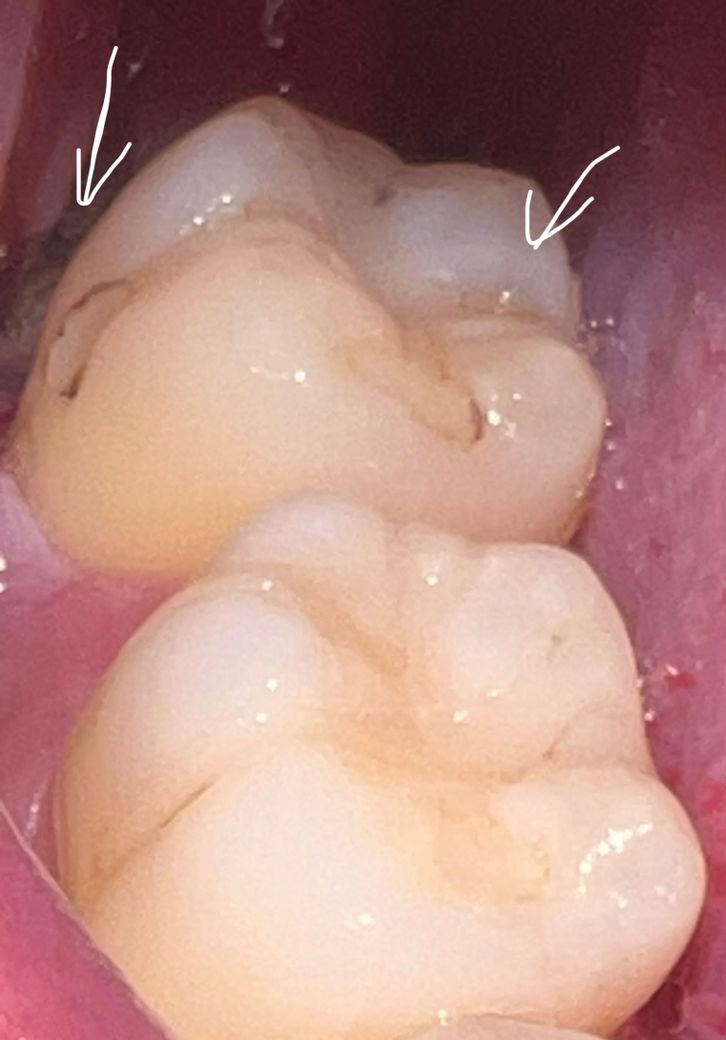

매복사랑니 바로 앞니 이거 혹시 충치인걸까요?

2주전에 매복사랑니 발치했는데 이번에 양치할때 보니까 사랑니 바로 앞에있던 치아가 거뭇거뭇 하더라고요 혹시 이거 충치인걸까요??

맞다면 레진 선에서 가능한걸까요 아니면 금니까지 해야하는걸까요?

충치보다는 치아와 레진 사이의 틈에 착색이 된 것으로 보입니다만 정확한 것은 치과진료가 필요합니다.

예전에 치료를 한 레진주변으로 착색이됫을 가능성도 잇으니 치과에 가셔서 일단 스켈링 및 착색제거를 해보시는게 좋을것같습니다.

사진으로만 봤을경우 이전에 사용한 재료에 착색이 된것으로 보입니다.

큰 치료가 필요해 보이지는 않습니다.